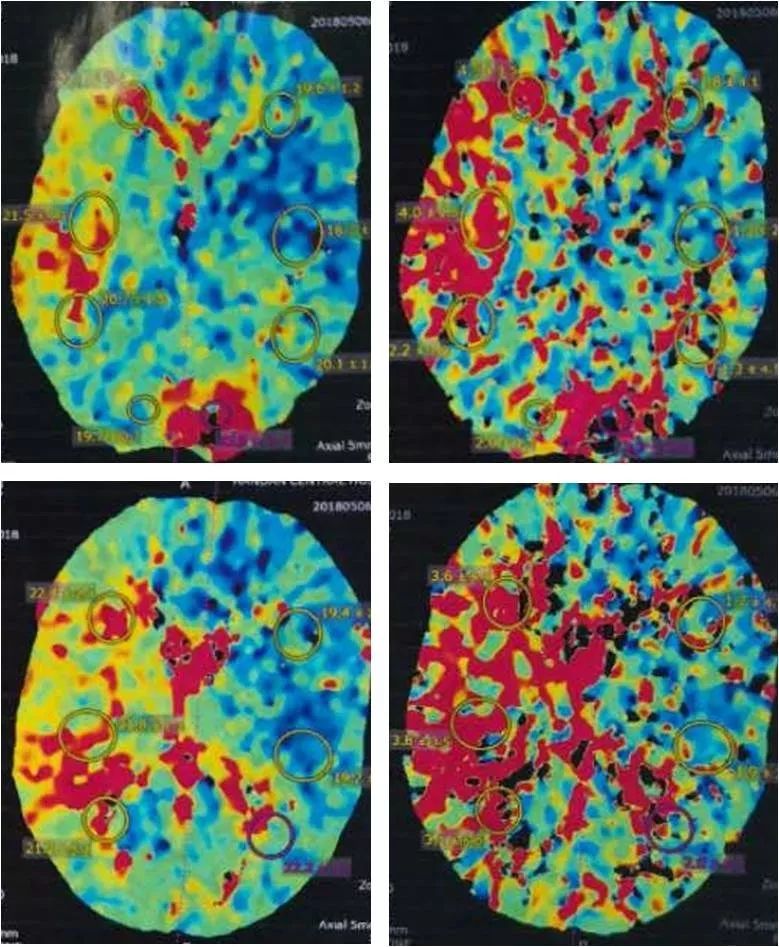

CTP:右大脑中动脉供血区低灌注(图6)。

图6